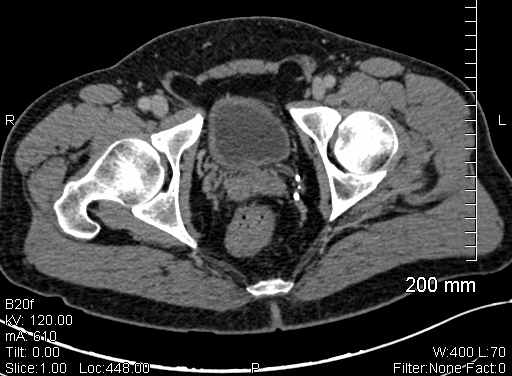

The study follows 3,546 men with prostate cancer, treated with prostate seed implants followed by external beam radiation therapy (EBRT). None of the men included in the study received pre-treatment hormone therapy. The implant procedure used in these patients was updated in 1992, given improvements in treatment techniques. From the sample, 73 percent had no evidence of prostate cancer 25 years after the irradiation program.